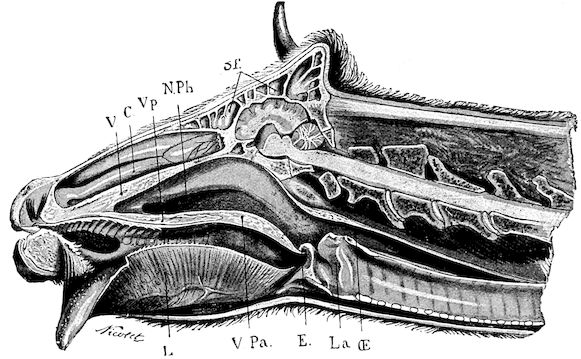

Fig. 1.—Rachitis in a young goat.